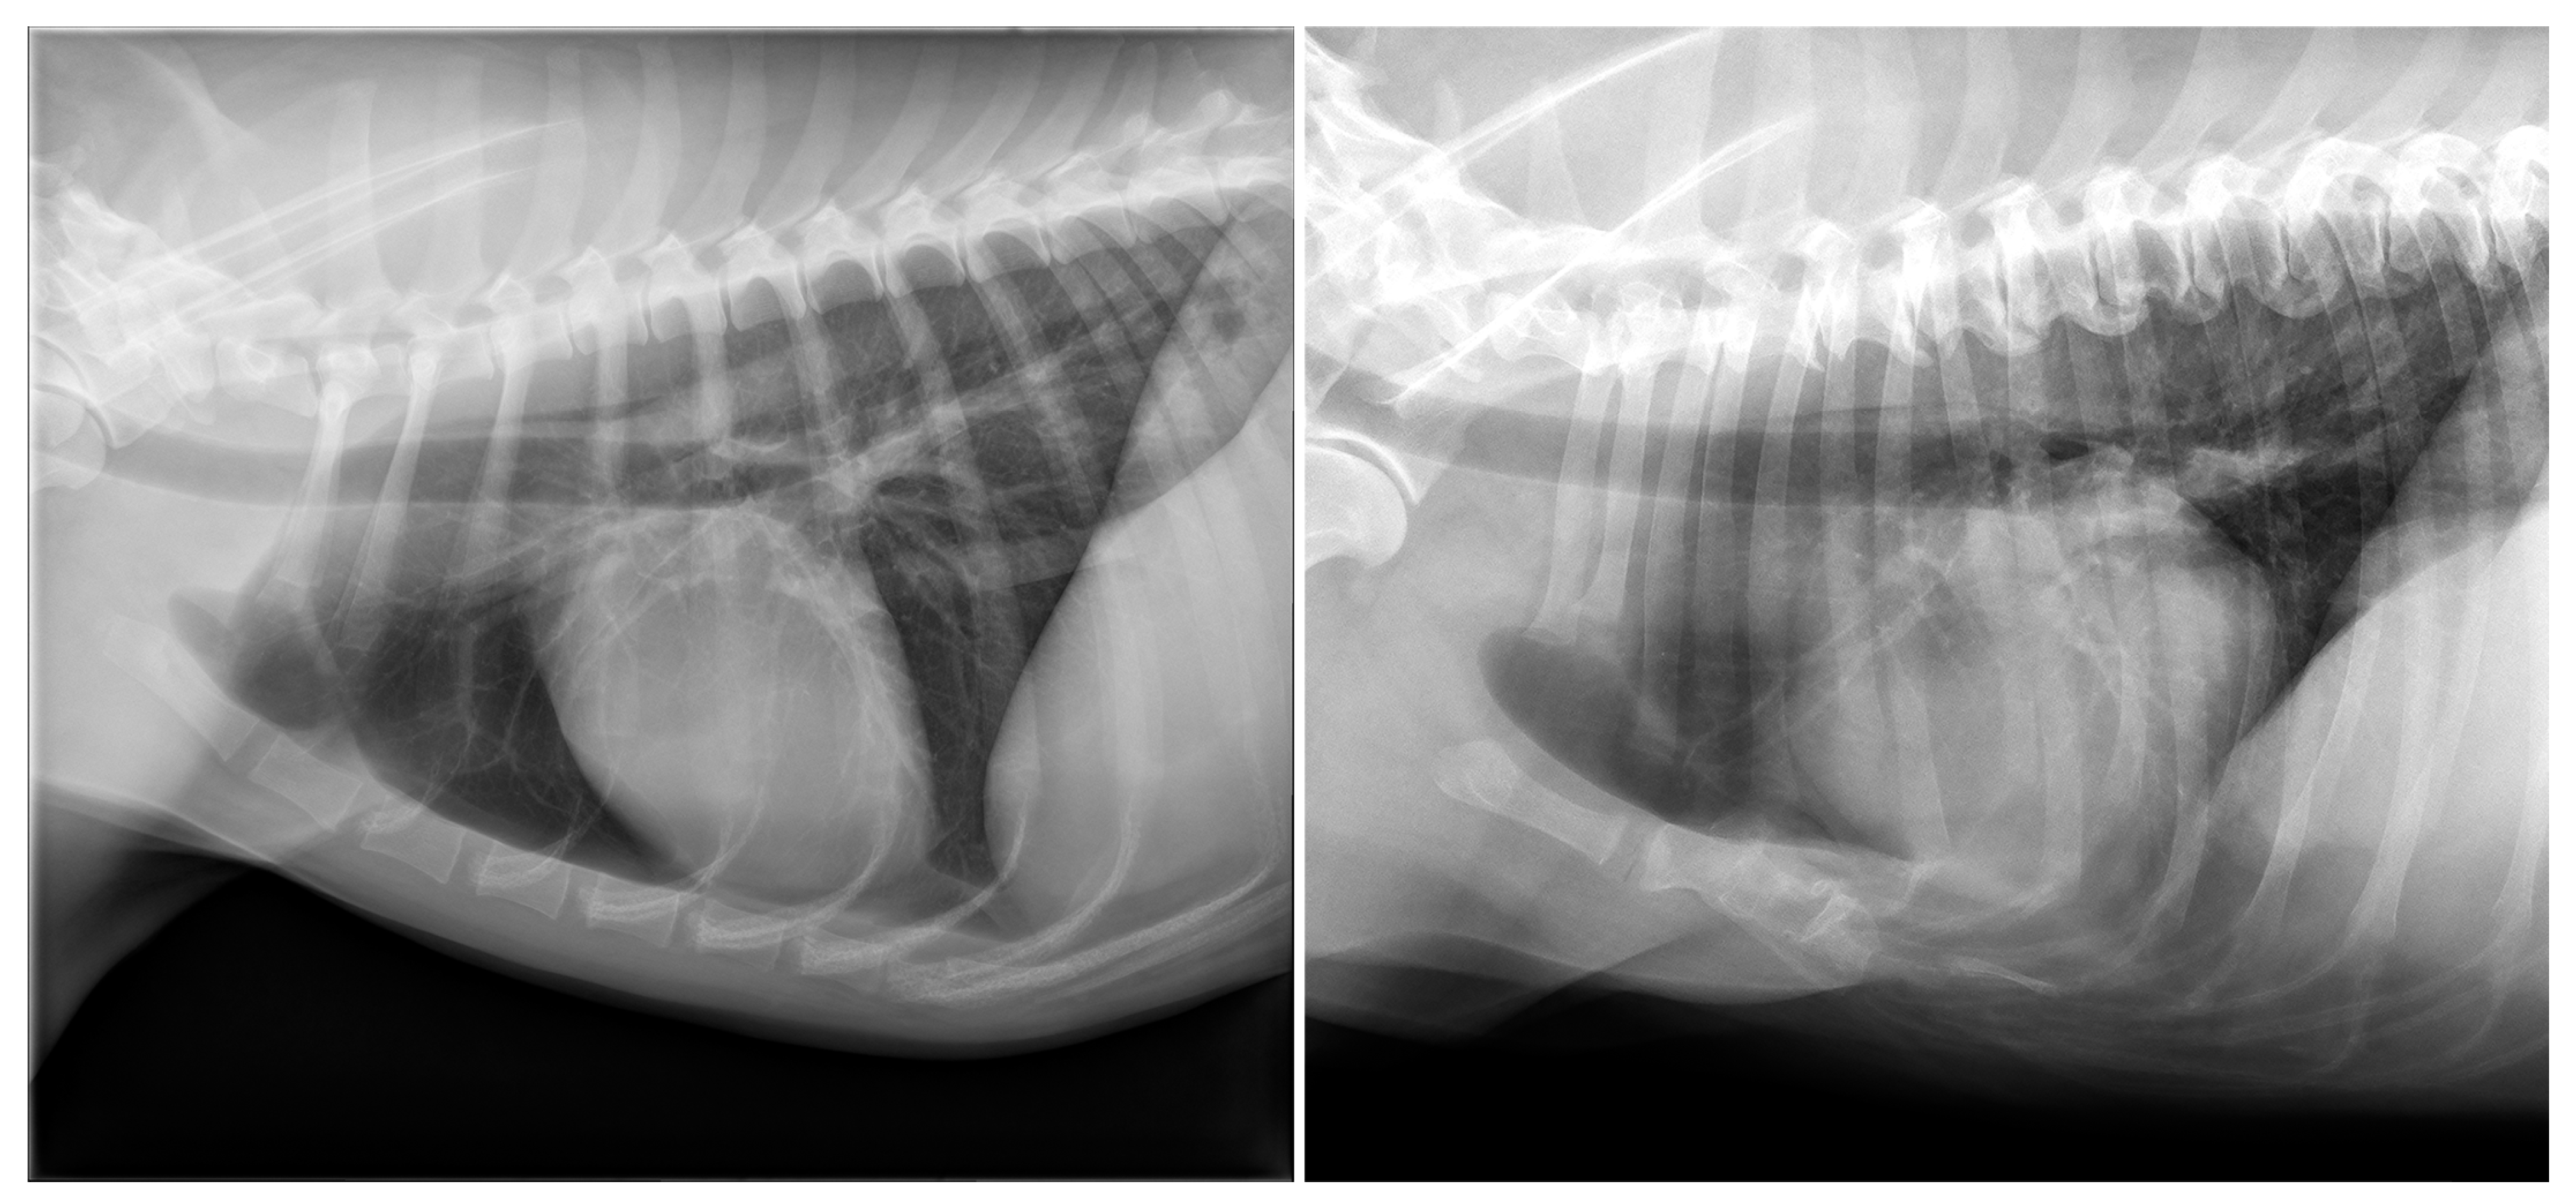

3.1. Dogs

3.2. Cats

| Shape deformity (n = 24) | Pectus excavatum (n = 6) | Pug (2/7); Boxer (1/13); Dachshund (1/19); French Bulldog (1/23); mixed (1/145) |

| Pectus carinatum (n = 18) | French Bulldog (8/23); Chihuahua (5/28); mixed (3/145); Pug (1/7); Welsh Springer Spaniel (1/3) | |

| Shape deformity (n = 8) | Pectus excavatum (n = 6) | Domestic Shorthair (6/112) |

| Pectus carinatum (n = 2) | Domestic Shorthair (1/112); Norwegian Forest (1/4) | |